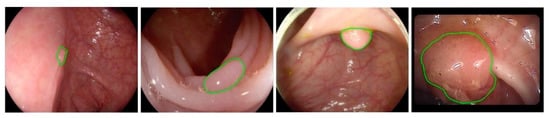

There are various challenges in the automated detection of polyps. As shown in Figure 1 and Figure 2, polyps appear in different sizes, shapes, textures, and color. Their endoscopic appearance can be similar to protruded lesions, flat elevated lesions, and flat lesions. The images even have noisy background with bleeding and endoluminal folds, which suppresses the accuracy of the detection process.

Figure 1.

Images with ground truth polyps (marked in green) from colonoscopy videos.